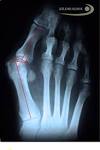

Hallux valgus: Diagnose, Behandlung und Operation